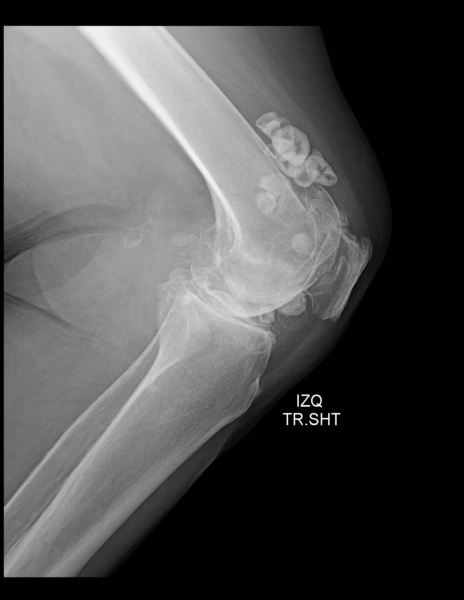

RADIOGRAFIA AP Y LATERAL DE RODILLAS.

Los tejidos blandos de ambas rodillas a nivel de grasa suprapatelar y periférica al articulación con presencia de imágenes radio pacas, redondeadas, irregulares, bien definidas, con centro sutilmente radiolúcido al resto de la periferia, de lado izquierdo miden desde 6.5 mm hasta 2.22 cm y de lado derecho desde 1.4 cm a 1.67 cm. Resto sin alteraciones.

Estructuras óseas; fémurs distal y tibias proximales, sin evidencia de lesiones líticas, blásticas o perdida de la contigüidad. Existen osteofitos marginales.

Rotulas, centrales, sin evidencia de lesiones líticas, blásticas o perdida de la contigüidad. Existen osteofitos marginales.

El espacio articular femorotibial, con disminución severa de su amplitud.

Espacio articular patelofemoral, con disminución severa de su amplitud.

Angulo femorotibial derecho de 173.6° e izquierdo de 174 °.

Angulo Muñiz derecho de 5° e izquierdo de 7.1°.

Índice de install-salvati derecho de 0.8 e izquierdo de 1.07.

EN EL PRESENTE ESTUDIO RADIOGRÁFICO, EXISTE GONARTROSIS SEVERA BILATERAL.

CALCIFICACIONES PERIARTICULARES EN TEJIDOS BLANDOS DE PREDOMINIO EN GRASA SUPRAPATELAR BILATERAL DE PREDOMINIO EN RODILLA IZQUIERDA.